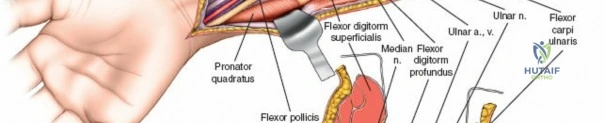

Exposure and Release of Deep Volar Compartment: This is the most critical and potentially challenging step. The median nerve and ulnar artery lie deep to the superficial flexor muscles.

- Median Nerve Protection: Retract the FDS radially. The median nerve typically lies beneath the FDS. It must be carefully identified and protected.

- Ulnar Nerve and Artery Protection: The ulnar nerve and artery run along the ulnar border, deep to the FCU. They are usually not directly in the field of the primary fasciotomy, but their fascial envelopes should also be released.

- Accessing the Deep Compartment: Separate the FDS radially from the FCU. Retract the FDS radially and the FCU ulnarly. The deep volar compartment, containing FDP, FPL, and PQ, is now accessible. The fascia overlying the FDP and FPL must be meticulously incised longitudinally. This deep release is crucial for adequate decompression.

This image illustrates the deeper dissection. The superficial flexor muscles (FDS) are retracted, exposing the median nerve and the underlying deep volar compartment. Note the care taken to protect the median nerve.

The median nerve and ulnar artery/nerve must be completely unroofed to ensure adequate decompression. This often requires releasing the entire carpal tunnel proximally to ensure distal decompression of the median nerve.

This detailed view highlights the median nerve (retracted by the yellow vessel loop) and the extensive release required, extending distally to encompass the carpal tunnel, ensuring complete decompression.Ensure that the deep fascia separating the FDS from the FDP and FPL is completely released. The anterior interosseous nerve and artery lie on the interosseous membrane and should also be decompressed by releasing the fascia overlying the deep flexors.

Further meticulous dissection showing the complete release of the deep volar compartment, with all muscle bellies visibly decompressing. Neurovascular structures are clearly identified and protected.